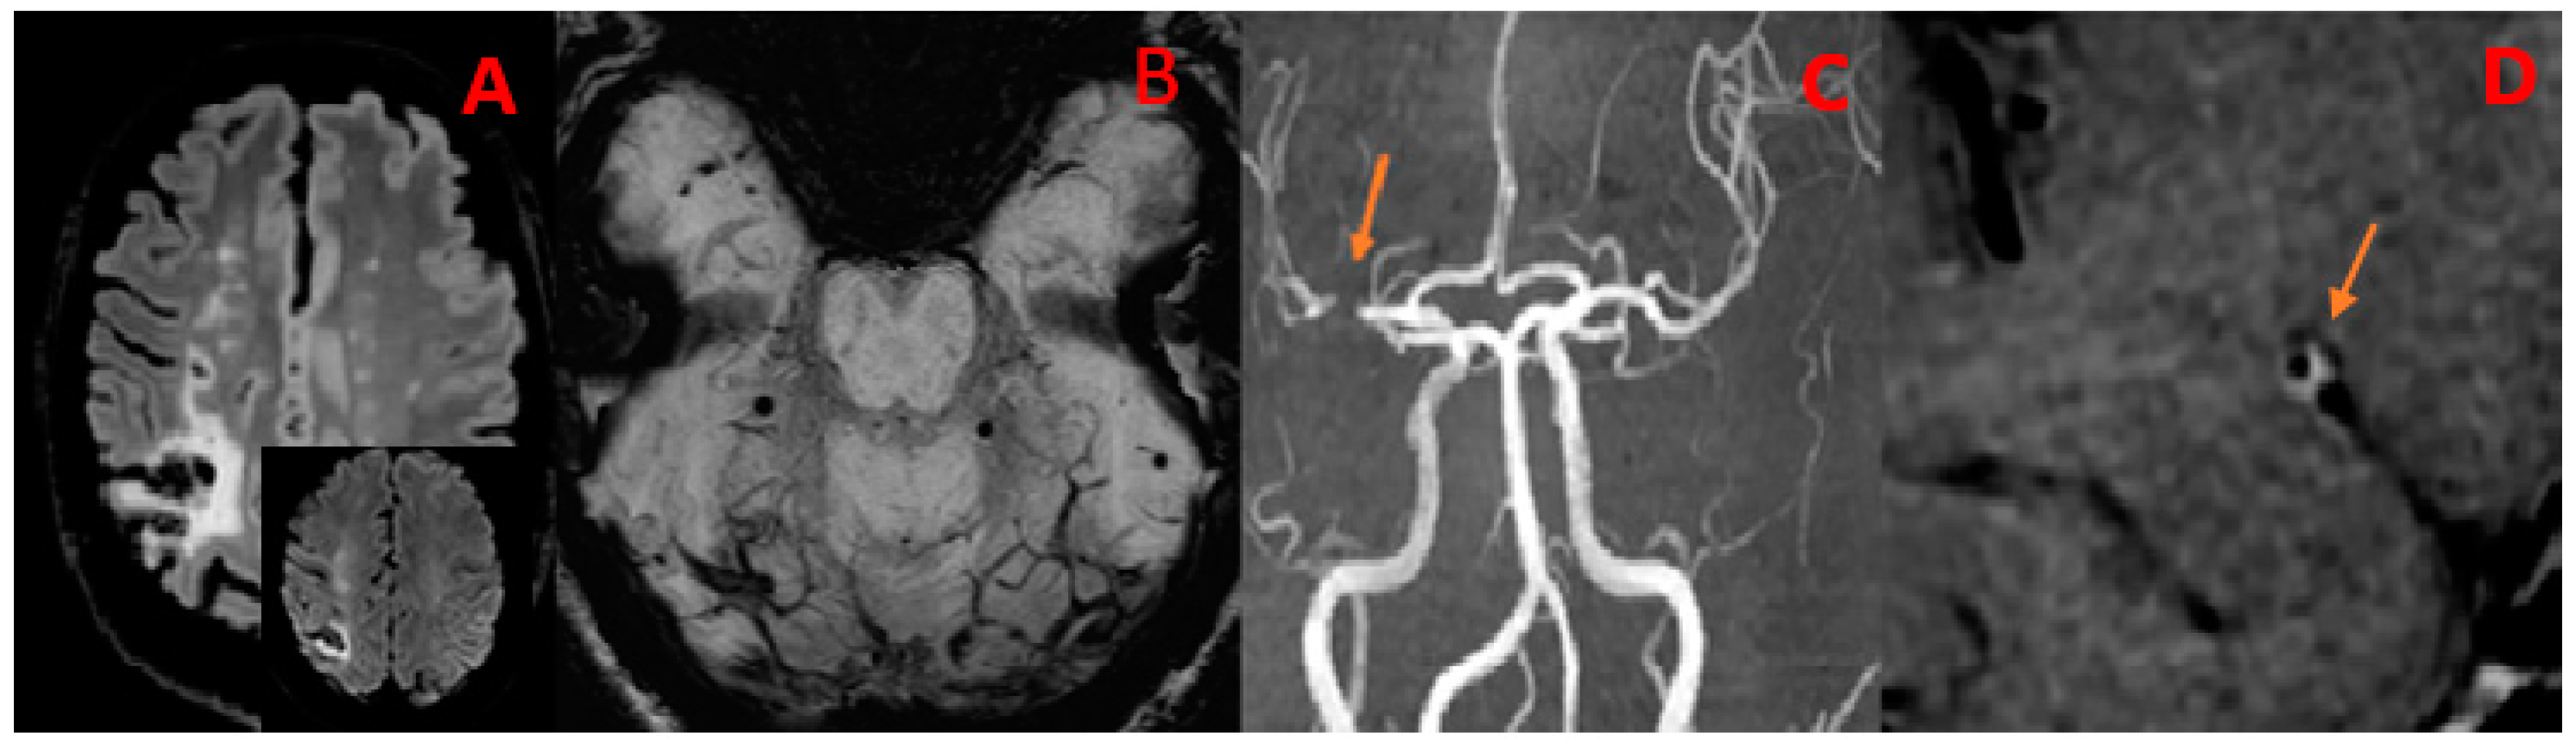

7. Legend

| 49Y, M | 1 | Present | Present | Multiple subcortical in MCA territories | ICA | MCA (M1) ACA (A1) | Present | Subtentorial |

| 58Y, M | 2 | Present | Present | Multiple subcortical in ACA and MCA territories and left SCA | ICA | None | Present | Supratentorial |

| 5Y, M | // | Absent | Absent | No | VA | BA | Present | Subtentorial |

| 39Y, F | 1 | Absent | Present | No | M1 | PCA (P1) | Absent | // |

| SCNSV Luetic (n = 2) | 2 (100.0%) | 2 (100.0%) | 0 (0.0%) | 0 (0.0%) | 2 (100.0%) | 2 (100.0%) | 1 (50.0%) multiple: 1 (100.0%) | 1 (50.0%) | 0 (0%) | 2 (100.0%) | 0 (0%) | ACM(M1), ACA(A1), ICA |

| SCNSV VZV-related (n = 1) | 0 (0.0%) | 0 (0.0%) | 0 (0.0%) | 0 (0.0%) | 0 (0.0%) | 1 (100.0%) | 1 (100.0%) | 1 (100.0%) | 0 (0%) | 1 (100.0%) | 0 (0%) | BA, VA |

| multiple: 1 (100.0%) | ||||||||||||

| SCNSV HIV/EBV-related (n = 1) | 1 (100.0%) | 0 (0.0%) | 0 (0.0%) | 0 (0.0%) | 1 (100.0%) | 0 (0.0%) | 1 (100.0%) multiple: 1 (100.0%) | 1 (100.0%) | 0 (0.0%) | 1 (100.0%) | 0 (0.0%) | ICA, ACA (A1), MCA (M1) |